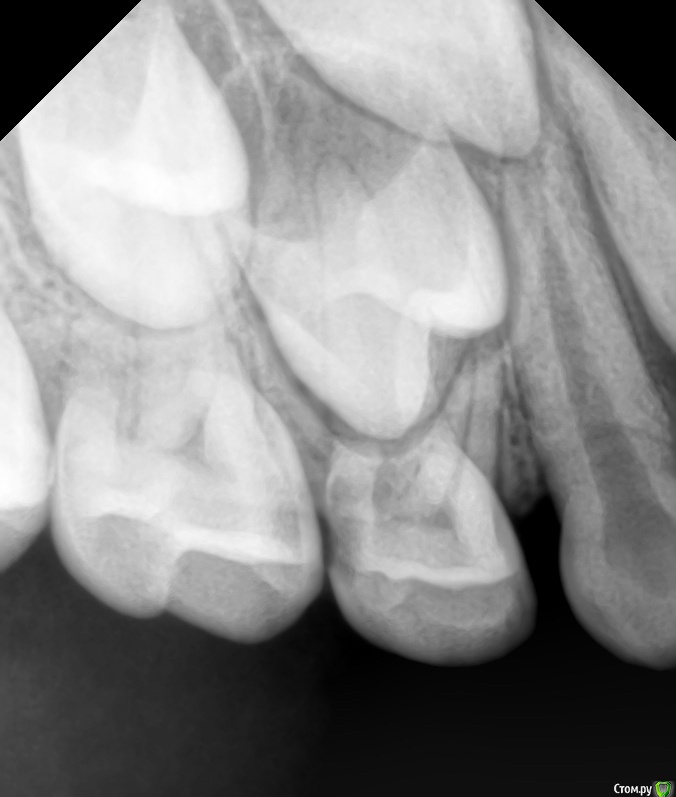

CRAZYDUCK Опубликовано 22 мая, 2018 Автор Поделиться Опубликовано 22 мая, 2018 (изменено) И про короночки ловите. 8.4 и 8.5 ранее ( около двух лет назад ) лечены методом витальной ампутации . Реставрации обширные плюс начался кариес контактных поверхностей . Два года назад я не применяла так широко в практике своей Коронки ( сейчас бы покрыла сразу после ампутации). Изменено 22 мая, 2018 пользователем CRAZYDUCK 1 Ссылка на комментарий

crown Опубликовано 22 мая, 2018 Поделиться Опубликовано 22 мая, 2018 8.4 похоже что есть изменения в бифуркации? Да надо возвращаться к коронкам. Вы где учились их ставить? Ссылка на комментарий

CRAZYDUCK Опубликовано 23 мая, 2018 Автор Поделиться Опубликовано 23 мая, 2018 В нижних 4 часто такая зона, даже в интактных. Я тоже на эту зону всегда недоверчиво смотрю. Я напишу Вам в личку позже где училась . 8.4 похоже что есть изменения в бифуркации? Да надо возвращаться к коронкам. Вы где учились их ставить? Ссылка на комментарий